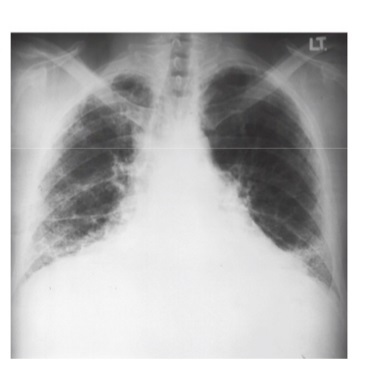

Identify Xray

Pulmonary Fibrosis